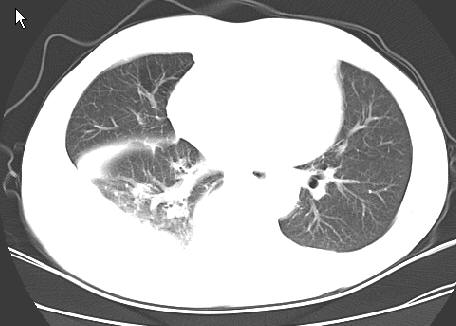

以下是引用草之原在2009-5-2 19:29:00的发言:[br]1.考虑右侧中心型肺ca纵膈淋巴结转移,双侧胸腔积液及右侧叶间裂积液,心包积液。[br]2.两肺上叶病灶,纵膈窗显示部分病灶硬化,考虑:结核。[br][br] [br]

以下是引用ct诊断高手在2009-5-2 19:08:00的发言:[br]我考虑右侧中央型肺癌 伴右肺节段性不张,两肺及纵隔淋巴结转移,右侧胸腔积液。

以下是引用zjzjr在2009-5-2 20:16:00的发言:[br]肺结核,转移瘤.纵隔淋巴结转移或淋巴瘤,右侧包裹性积液、斜裂积液。心包积液。